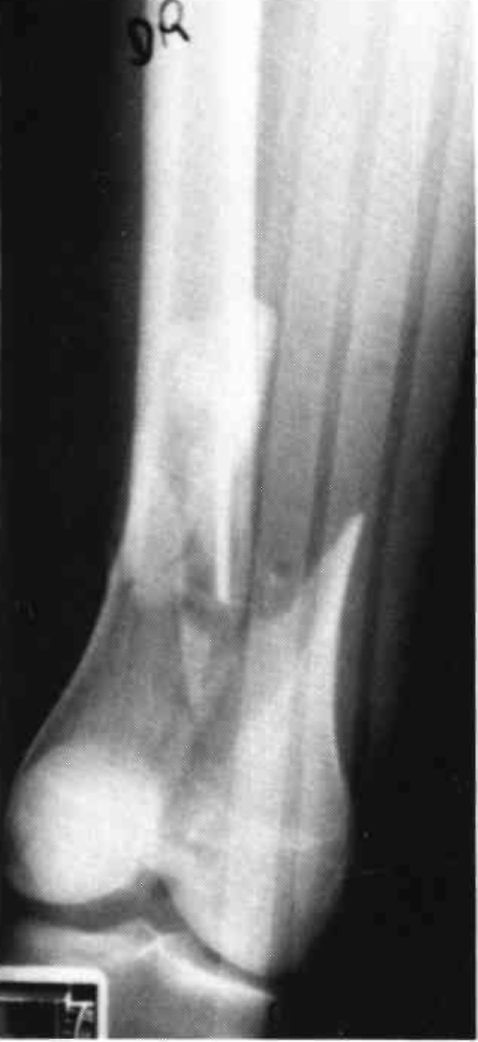

A twenty-five year old female sustained a fracture dislocation of the left knee (Fig. 8). The fracture and ligaments were internally fixed, and the patient was placed in a continuous passive motion dynamic suspension system utilizing a Mobilizing Brace (3 D) and a bootie (Fig. 9). The patient achieved 0-90° of motion in two days and was maintained in passive motion for five days until she could achieve the same range of motion actively without excessive pain. The patient was then cast braced for increased medial-lateral stability, received gait training, and was discharged from the hospital.

Figure 8:

Figure 9: